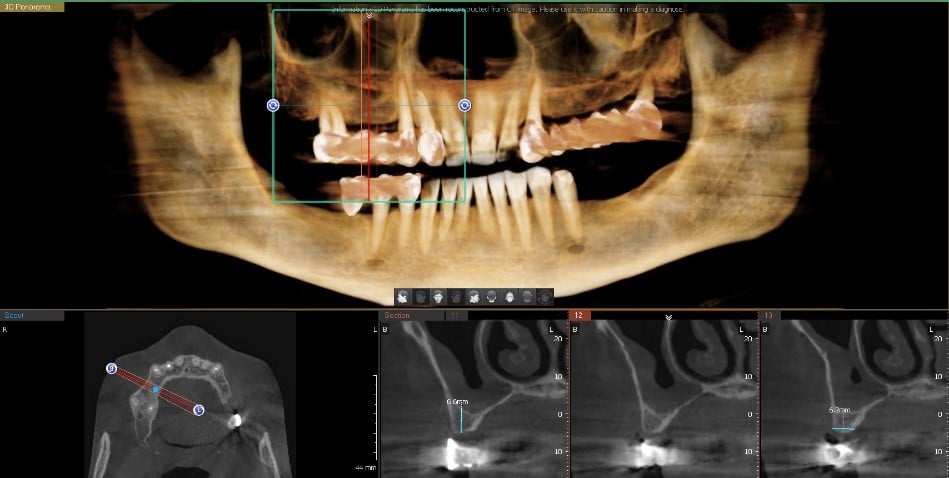

Planul inițial a fost extracția dinților 16 și 28 și inserarea implanturilor în pozițiile 14, 15, 17, 24, 26, 27.

În urma evaluării CBCT-ului s-a constatat necesitatea realizării augmentarii osoase ăn zona posterioară maxilară, lifting sinusal maxilar bilateral odată cu inserarea implanturilor.

Pentru a se asigura că implanturile dentare vor fi plasate în poziția ideală din punct de vedere estetic și funcțional, medical implantolog a recomandat inserarea implanturilor dentare cu ajutorul ghidului chirurgical.

Medicul specialist a efactuat scanarea digitală a arcadelor pe care a trimis-o tehnicianului dentar DigiRay, împreună cu CBCT-ul pacientului.

Odată planficată și agreată poziția și axul de inserție al fiecarui implant, tehnicianul DigiRay efectuează designul șablonului chirurgical și printarea acestuia dintr-o rășină bio-compatibilă.